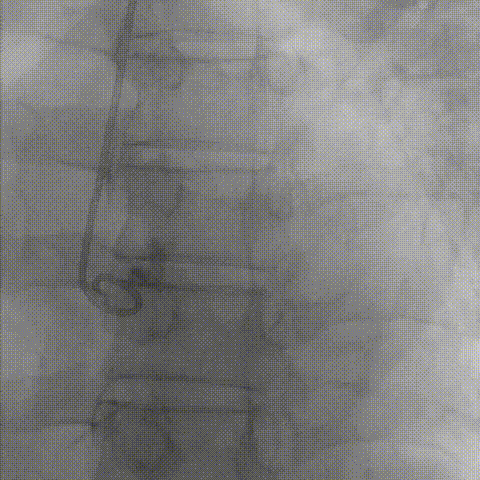

患者病史 主诉:发作性胸闷憋喘半年,加重伴呼吸困难2周。 现病史:患者半年前无明显诱因出现胸闷、憋喘,伴有下肢水肿,2周前上述症状明显加重,夜间不能平卧,痰中带血丝,为进一步诊治再次来我院,门诊以"心力衰竭"收入院。 既往史:肾功能不全、心房颤动 心脏超声提示:LVEF:0.54 1.主动脉瓣病变;2.主动脉瓣狭窄(重度)并反流(中度);3左室壁节段性运动不良;4.升主动脉扩张、双房扩大、左室肥厚;5.二尖瓣硬化并反流(中度);6.三尖瓣反流(轻-中度);7.肺动脉瓣反流;8.肺动脉高压(轻度)PGmean=105mmHg,Vmax=635cm/s,瓣口面积0.27cm²。 术前CT评估 Type0型二叶瓣,重度钙化,钙化集中在瓣叶游离缘,右冠窦为著;左冠高度11.8mm,由于左冠窦部空间较小,左冠风险较高, 升主动脉扩张,最宽处50.5mm;主动脉瓣环水平夹角61.5°,横位心。主动脉弓角77.6°,锐角弓,外周入路在腹主及髂总处有大量散状钙化,胸主处有81.6°的迂曲。 手术策略 推荐右侧股动脉为主入路,左侧股动脉为辅入路,送snare辅助过弯,使用18F大鞘,推荐预装ProStyle A® AV23瓣膜,20mm球囊预扩,初始定位对齐真实瓣环瓣上5mm超高位初始定位释放,释放过程中使瓣膜自然下滑,到工作位观察瓣膜形态,最终理想位置0-瓣下3mm。 手术过程 Step1:右侧股动脉为主入路、左侧股动脉为辅入路,成功穿刺并送入 18F 大鞘; Step2:主动脉根部造影,瓣口限制重 Step3:Type 0 型二叶瓣畸形合并重度钙化,患者瓣口狭窄严重,同时横位心,不仅导丝跨瓣困难,导管更难进入;术者凭借精湛操作,将导丝顺利跨瓣,反复微调导管角度,最终导管顺利过瓣。 导丝精准跨瓣 Step4:20mm球囊跨瓣困难,snare辅助下球囊成功跨瓣,预扩有腰无漏,冠脉充盈良好。 Step5: snare辅助下成功跨瓣,可以看到系统过弓形态瓣膜仓柔软,过弓顺滑 输送系统过弓 Step6:初始定位瓣上5mm开始释放,释放部分后观察瓣架下缘内收明显,后回收系统重新定位 初始定位 底部内收 Step7:瓣膜完全释放前,血压一度降低,术者迅速调整器械,实现瓣膜迅速锚定,快速释放 完全释放 Step8:20mm球囊后扩 最终造影,位置(瓣下3mm)形态良好 手术难点 患者不仅有主动脉瓣重度狭窄,还叠加肾功能不全、心房颤动等基础疾病,术中血流动力学波动极易引发心功能衰竭。ProStyle A® 预装干瓣“开包即用” 的特性压缩了术者操作时间,80%可回收设计给了术者容错空间,而这些看似难以逾越的难关,最终被团队精湛的医术一一化解,术中对于导丝、导管、球囊等器械每一步的精准操控,再到突发状况的从容处置,无不彰显着团队深厚的专业积淀与顶尖的操作技艺。 结语 此次手术的圆满成功,不仅彰显了陈玉国、李传保教授团队在复杂结构性心脏病介入治疗领域深厚的专业造诣与攻坚克难的决心,也充分验证了ProStyle A®系统在应对复杂高难度病例时的卓越适用性与有效性。 作为扎根齐鲁、享誉全国的医疗高地,山东大学齐鲁医院始终赓续着这片热土的仁厚文脉,将“医道从德,术业求精”的院训精神镌刻在每一次诊疗实践之中。特别是在结构性心脏病诊疗领域,医院团队始终怀揣医者担当,勇攀医学高峰,不断以更前沿的技术突破,为危重患者点亮重获新生的希望。 专家简介 陈玉国 山东大学齐鲁医院(点击查看专家详细简历) 李传保 山东大学齐鲁医院(点击查看专家详细简历) · END ·